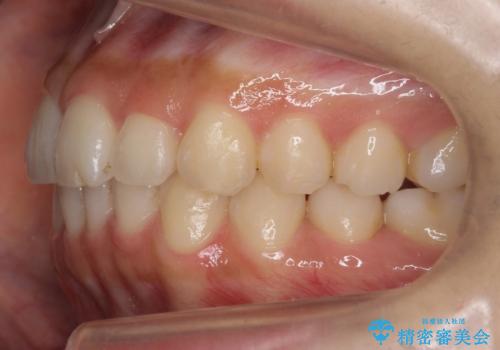

犬歯のねじれ 下の歯のがたがた インビザラインで

- 右上の犬歯のねじれ、下の歯のがたつきを主訴に来院。

インビザラインで歯を抜かずに並べました。

初回:上顎16ステージ 下顎22ステージ

リファインメント: 上顎23ステージ 下顎20ステージ

下の前歯のがたがたがそれなりにあったため、リファインメントを行いました。